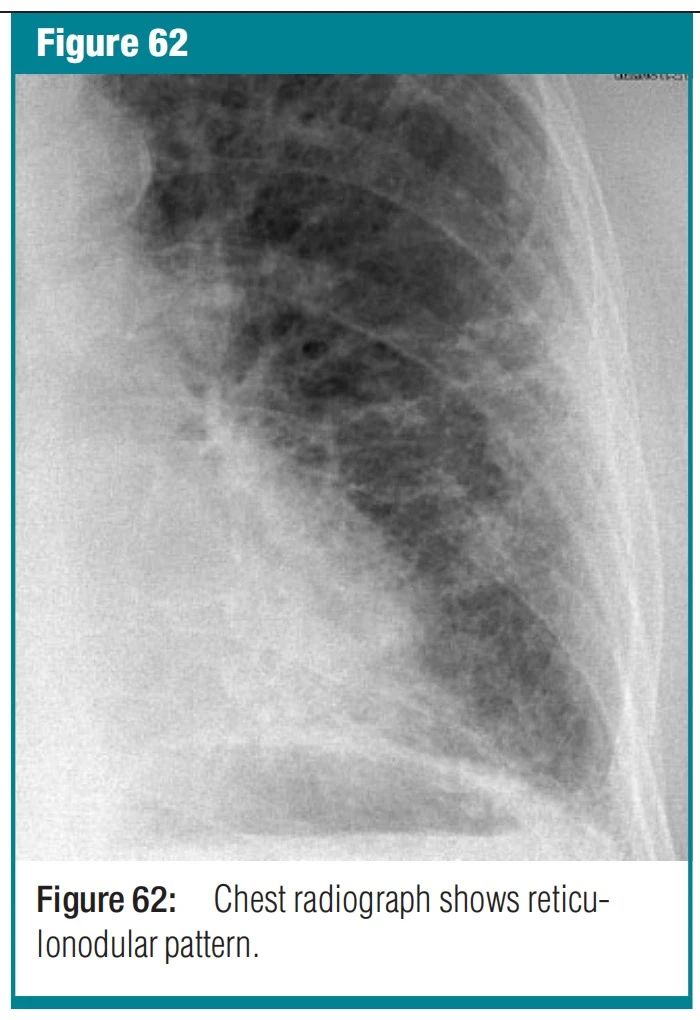

图9 reticular pattern-网状影 X 光照片和 CT 扫描-在胸部 X 光照片上,网状影是无数细小的线性不透明物的集合,通过总和,产生类似于网的外观(同义词:网状结构)。这一发现通常代表间质性肺疾病。网状结构的组成部分在薄层 CT 上可以更清楚地看到,无论是小叶间间隔增厚、小叶内线还是蜂窝状囊壁。